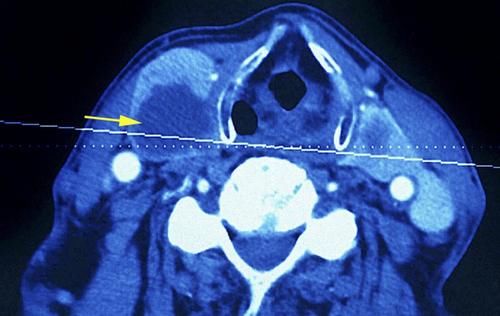

导语:众所周知,甲状腺是一个很小的内分泌器官,形状似“H”,位于脖颈前部,喉咙两侧,因为过于脆弱,所以稍有不慎,就可能损伤甲状腺,导致甲状腺结节的出现。

也就在她辞职的不久后,小丽查出了甲状腺结节,好在结节是良性的,医生让她少生气,多注意休息,结节很快就能消散,她自己也没放在心上。

【 榴莲|女子查出甲状腺结节,半年后转癌?医生:这3种水果可不能多吃】经过复查,小丽的甲状腺结节不仅没有消散,反而恶化,有些甲状腺细胞已经癌变,这让她接受不了。